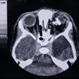

- Linear Nevus Sebaceous Syndrome

- linear nevus sebaceous syndrome, CT scan

- CT scan of linear nevus sebaceous syndrome.